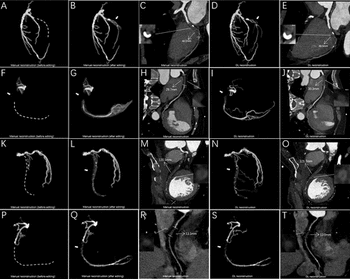

In the newly released Lung-RADS 2022 classification system for computed tomography (CT) lung cancer screening, the American College of Radiology (ACR) has noted a variety of updates including new classification criteria for atypical pulmonary cysts and airway nodules, time intervals for nodule growth and a new stepped management approach for Lung-RADS categories 3 and 4A.